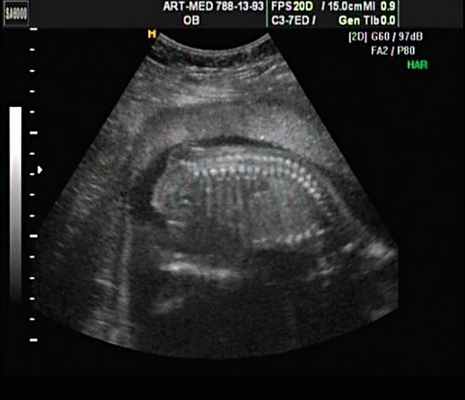

Ребенок от первой беременности после экстракорпорального оплодотворения. Беременность протекала с угрозой прерывания в I триместре, по поводу чего мать получала стационарное лечение. На сроке беременности 29 нед по данным УЗИ поставлен диагноз: врожденный порок развития - тератома, кистозное образование в области копчика (рис. 1). Родоразрешение на сроке гестации 39 нед путем кесарева сечения. Масса при рождении 3050 г, окружность головы 34 см, окружность груди 32 см, рост 50 см. Оценка по шкале Апгар 7/7.

В 30 нед фетометрические показатели плода соответствовали сроку беременности. Сколиотическая деформация позвоночника сохранялась. Дополнительно выявлена оболочечная грыжа, исходящая из грудного отдела позвоночника, в области деформированных позвонков. Грыжа представляла собой стебельчатой формы образование с суженной ножкой (рис. 7, 8). Концевая часть ее была расширена в виде петли и заполнена анэхогенным содержимым (ликвором), которое отчетливо дифференцировалось на фоне "мутных" околоплодных вод (рис. 9). Таким образом, диагноз был уточнен: spina bifida - менингоцеле.